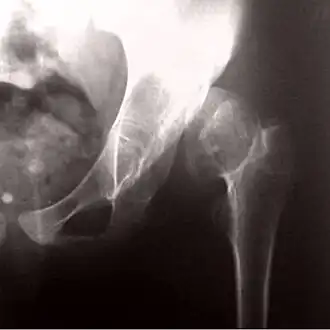

![]() Рентгенограмма, демонстрирующая развитие псевдоартроза при врожденном вывихе бедра | |

Врожденный вывих бедра также может стать причиной возникновения псевдоартроза.

Псевдоартро́з (либо «неоартро́з») — это ложный сустав, образовавшийся на несвойственном ему месте вследствие длительно существующего вывиха, либо длительно не сросшегося перелома при отсутствии должной медицинской помощи. Он образуется, как правило, после трёх—шести месяцев после травмы[1].

Диагноз ставится на основании рентгеновских снимков в двух взаимно перпендикулярных проекциях и клинических проявлений.